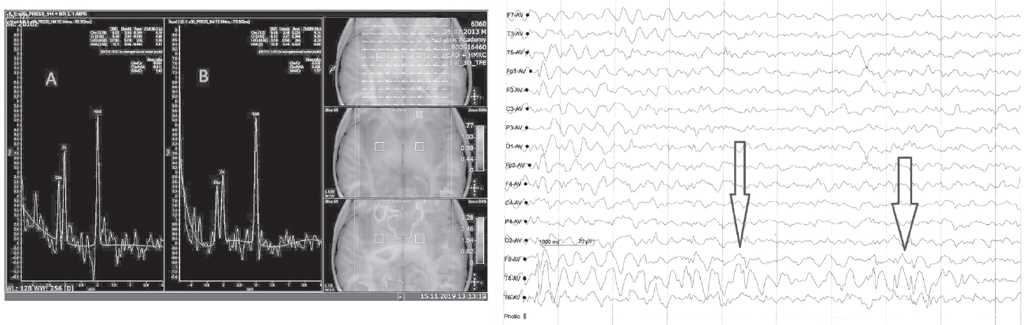

Обсуждение. Для определения концентрации нейрометаболитов в тканях головного мозга у пациентов использовали мультивоксельную протонную магнитно-резонансную спектроскопию (методом PRESS). У пациентов с задержкой психоречевого развития, ассоциированной с височной эпилепсией, выявилось снижение соотношения концентраций NAA/Cr (p < 0,05) в постцентральной извилине справа, височной доле справа и гиппокампах и внутренней капсуле с обеих сторон за счет снижения концентрации N-ацетиласпартата; увеличение соотношения концентраций Cho/Cr (p < 0,05) в префронтальной коре, постцентральных извилинах и внутренней капсуле с обеих сторон за счет повышения концентрации холина. У двух пациентов также обнаружены пики липидов на стороне поражения при сопоставлении с данными электроэнцефалограммы.